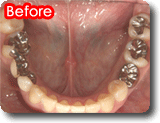

<症例1>

左下第二小臼歯クラウン治療部(歯根部が先天的に異常で短い)をインプラントへ